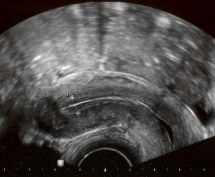

Transvaginale echoscopie

Met behulp van een transvaginale echoprobe die in de vagina wordt gebracht, wordt de groei van de eiblaasjes en het baarmoederslijmvlies gevolgd.

De blaas moet leeg zijn voor een optimaal echobeeld.

Figuur 6. Eierstok met meerdere groeiende eiblaasjes en baarmoederslijmvlies (tussen plusjes).